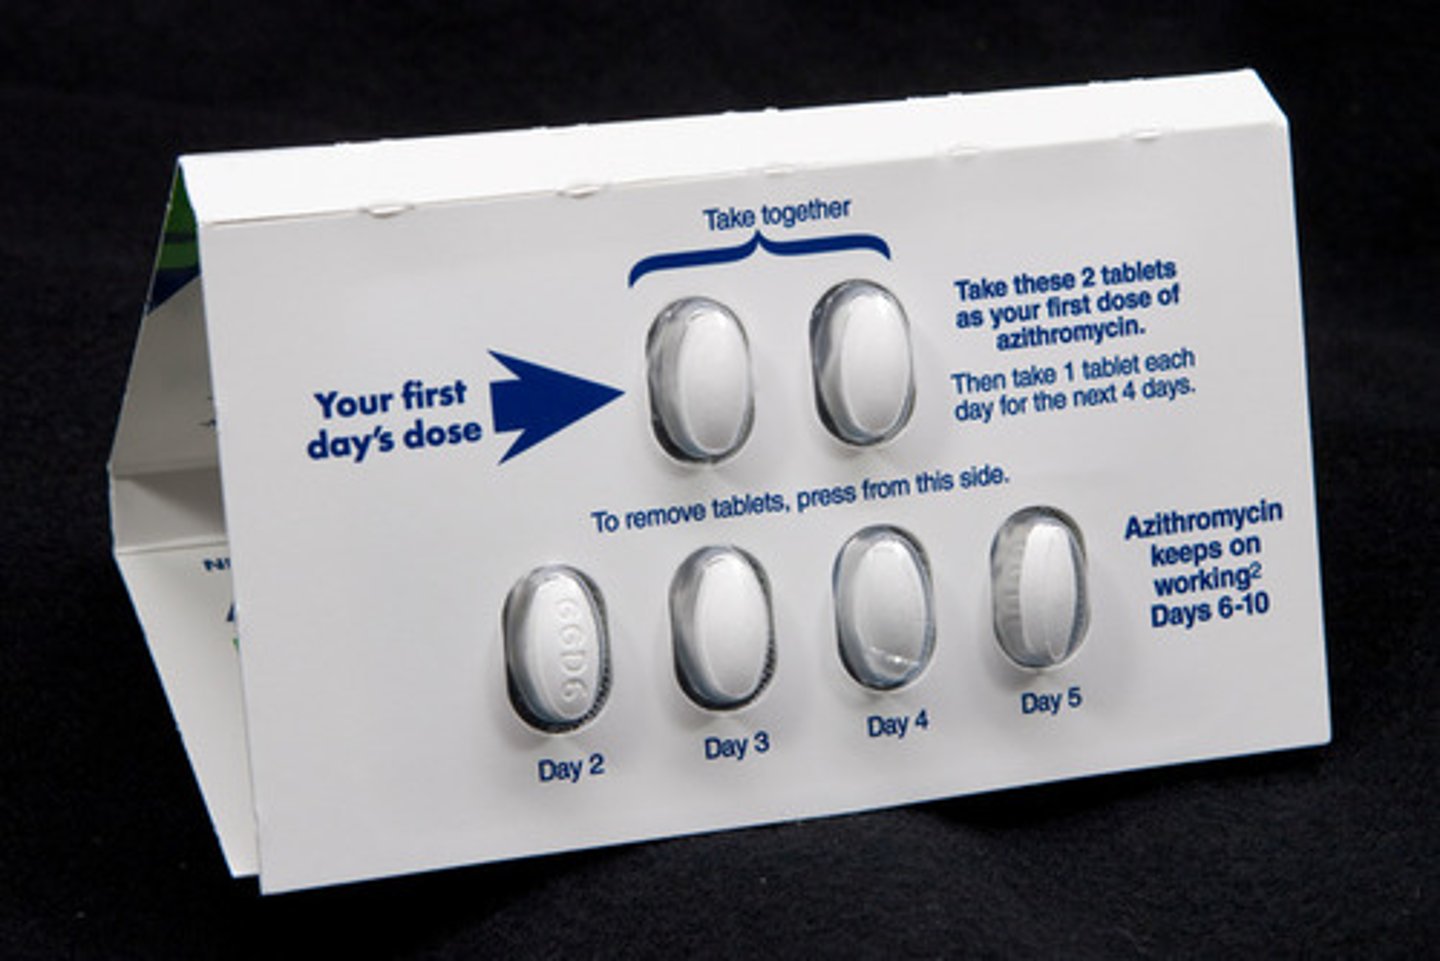

Azithromycin

Brand: Zithromax

Class: Macrolide Antibiotic

Drug Interactions:

1) reduce effectiveness of birth control

2) Increased risk of bleeding with anticoagulants

Indication: Bacterial Infection

Schedule: NCLM